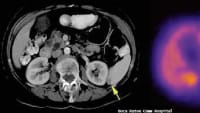

Until now, livers could be stored safely outside the body for only a few hours. With the novel perfusion technology, livers — and even injured livers — can now be kept alive outside of the body for an entire week. This is a major breakthrough in transplantation medicine, which may increase the number of available organs for transplantation and save many lives of patients suffering from severe liver disease or a variety of cancers.

Injured cadaveric livers, initially not suitable for use in transplantation, may regain full function while perfused in the new machine for several days. The basis for this technology is a complex perfusion system, mimicking most core body functions close to physiology. The corresponding study was published in the journal Nature Biotechnology1

The inaugural study shows that six of 10 perfused poor-quality human livers, declined for transplantation by all centers in Europe, recovered to full function within one week of perfusion on the machine. The next step will be to use these organs for transplantation. The proposed technology opens a large avenue for many applications offering a new life for many patients with end-stage liver disease or cancer.